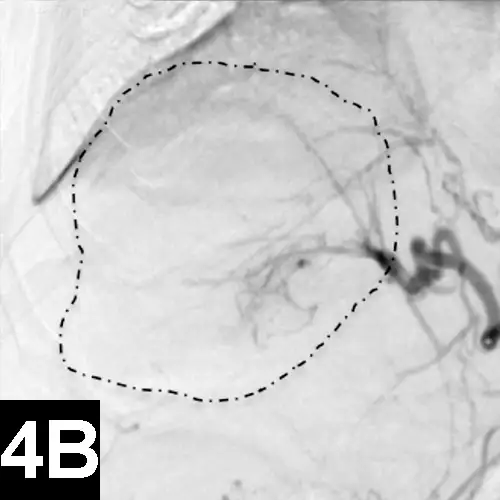

Figure 4A: Lateral digital subtraction angiograms of a dog with a nonresectable massive right-sided hepatocellular carcinoma.

The dog’s head is to the left.

Prechemoembolization angiogram demonstrating a massive liver tumor (surrounded by hyphenated line).

The author has performed this procedure in cases of invasive sinus carcinomas and unresectable hepatocellular carcinomas in dogs with encouraging results.13

When chemoembolization is performed in dogs, the author has documented as low as 1/20th the peak concentration of circulating chemotherapeutic agent found systemically as well as systemic chemotherapy exposure, which in turn theoretically reduces the toxic systemic side effects and subsequently results in improved tumor response rates when compared with intravenous administration.